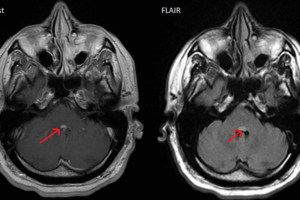

Facial colliculus MRI

Facial colliculus

The facial colliculi sit on the dorsal aspect of the pons, forming part of the floor of the fourth ventricle. Both facial colliculi are highlighted in the image below. Read more »